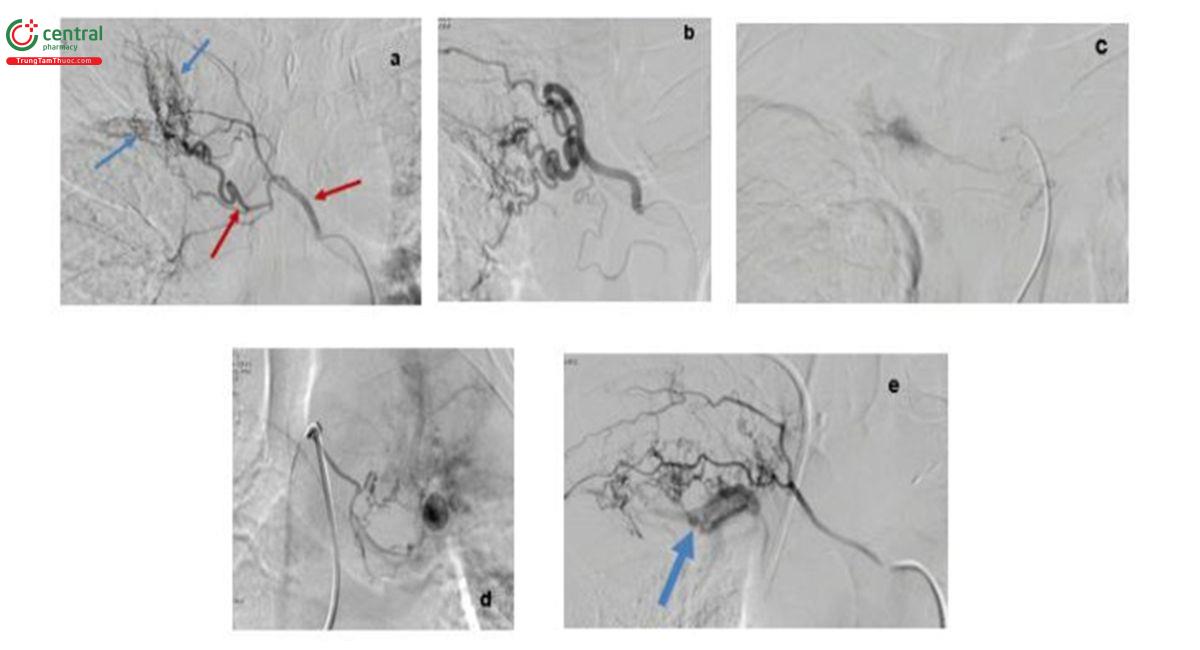

7.4 Hình ảnh chụp mạch số hóa xóa nền các bệnh nhân ho ra máu

Dấu hiệu “thoát mạch thuốc cản quang” (Hình 4c) là dấu hiệu trực tiếp xác định vị trí chảy máu. Dấu hiệu gián tiếp bao gồm: (1) Thay đổi hình thái ĐMPQ (giãn, phì đại gốc, xoắn vặn hoặc tăng sinh các mạch máu ngoại biên); (2) Dấu hiệu thông nối giữa ĐMPQ và tuần hoàn phổi (hình 4e); (3) Dấu hiệu giả phình mạch (Hình 4d). Động mạch có một trong những dấu hiệu gián tiếp này được xem là động mạch bệnh lý và có chỉ định gây tắc mạch. Mặc dù thoát mạch thuốc cản quang là dấu hiệu trực tiếp, đặc hiệu nhất cho xác định vị trí xuất huyết, tuy nhiên tần suất gặp rất ít, chỉ khoảng từ 1,7-19,1% [2,3]. Có thể do chảy máu từ ĐMPQ thường theo từng đợt, không liên tục và tốc độ chậm, các bệnh nhân đều được sử dụng với các thuốc co mạch, cầm máu trước thủ thuật.

Việc thuyên tắc các động mạch chủ yếu dựa vào các dấu hiệu gián tiếp thay đổi về hình thái của ĐMPQ. Giãn xoắn vặn gốc ĐMPQ (Hình 4b) là kiểu hình đặc trưng của ĐMPQ trong các bệnh lý nhiễm khuẩn, mạn tính như lao phổi. Phì đại gốc khi đường kính gốc động mạch >3mm, xoắn vặn mô tả động mạch uốn lượn hơn hai vòng ngược nhau từ gốc [5]. Đó là quá trình sinh lý bệnh, đáp ứng lại tình trạng thiếu máu phổi mạn tính và giảm tưới máu từ ĐMP dẫn đến tình trạng phì đại, giãn lớn để duy trì đủ lượng máu đến phổi bệnh lý. Hiệp hội hình ảnh và can thiệp lồng ngực Ấn

Độ cũng khuyến cáo các trường hợp HRM lượng ít nhưng chụp CTA cho thấy ĐMPQ giãn phì đại được tiến hành can thiệp sớm có thể giảm thời gian nằm viện [5].

Dấu hiệu “tăng sinh mạch máu ngoại biên” (Hình 4a) mô tả tăng lấp đầy thuốc cản quang với hình ảnh ửng sáng hoặc thâm nhiễm nhu mô phổi ngoại biên. Dấu hiệu thông nối với tuần hoàn phổi (ĐMP, tĩnh mạch phổi) được xác định trên hình chụp mạch khi bơm cản quang vào ĐMPQ, thấy hiện hình các nhánh của tuần hoàn phổi. Sự hiện diện của thông nối ảnh hưởng lựa chọn vật liệu thuyên tắc. Không sử dụng hạt <300µm để tránh nguy cơ hoại tử phổi. Có thể sử dụng coils để giảm lưu lượng thông nối hỗ trợ thuyên tắc [4]. Phình mạch suất độ trong 3,4-14,7% trường hợp có thể từ ĐMPQ, ĐMHTKPQ và ĐMP [2,3]. Giả phình mạch có thể hình thành do vỡ các thông nối phế quản - phổi. Cơ chế khác là tình trạng viêm làm suy yếu thành mạch, với sự thay thế lớp áo giữa và áo ngoài ở bệnh nhân lao phổi đang hoạt động, dẫn tới hình thành phình mạch Rasmussen. Do không có đầy đủ các lớp thành mạch như phình mạch thật sự, giả phình không ổn định, nguy cơ vỡ rất lớn, nên được khuyến cáo phình mạch cần can thiệp ngay khi chẩn đoán.